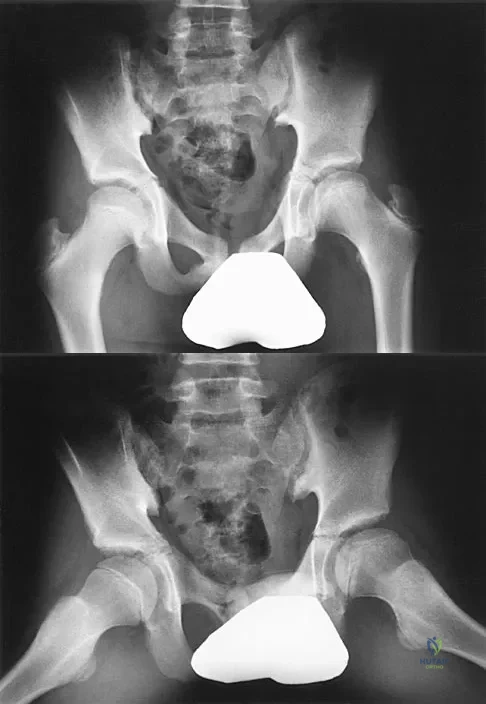

Figures 8a and 8b show the current radiographs of a 10-year-old boy with a hip disorder who was treated with an abduction orthosis 3 years ago. If no further remodeling occurs, what is the most likely prognosis?